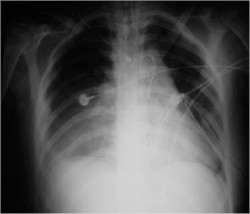

6 Comments Published by JonMikel, M.D. January 23rd, 2006 in Medical ImagesA previously healthy 17 yo woman came in to the ER because she has suffer an automovilistic accident. On the initial evaluation she was with pulse ‘parvus et tardus’ with altered mental status. A chest x-ray was ordered and found an aortic rupture.